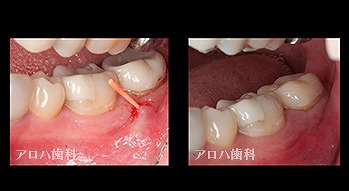

case3

再根管治療

1年予後

瘻孔の消失

頬側の瘻孔